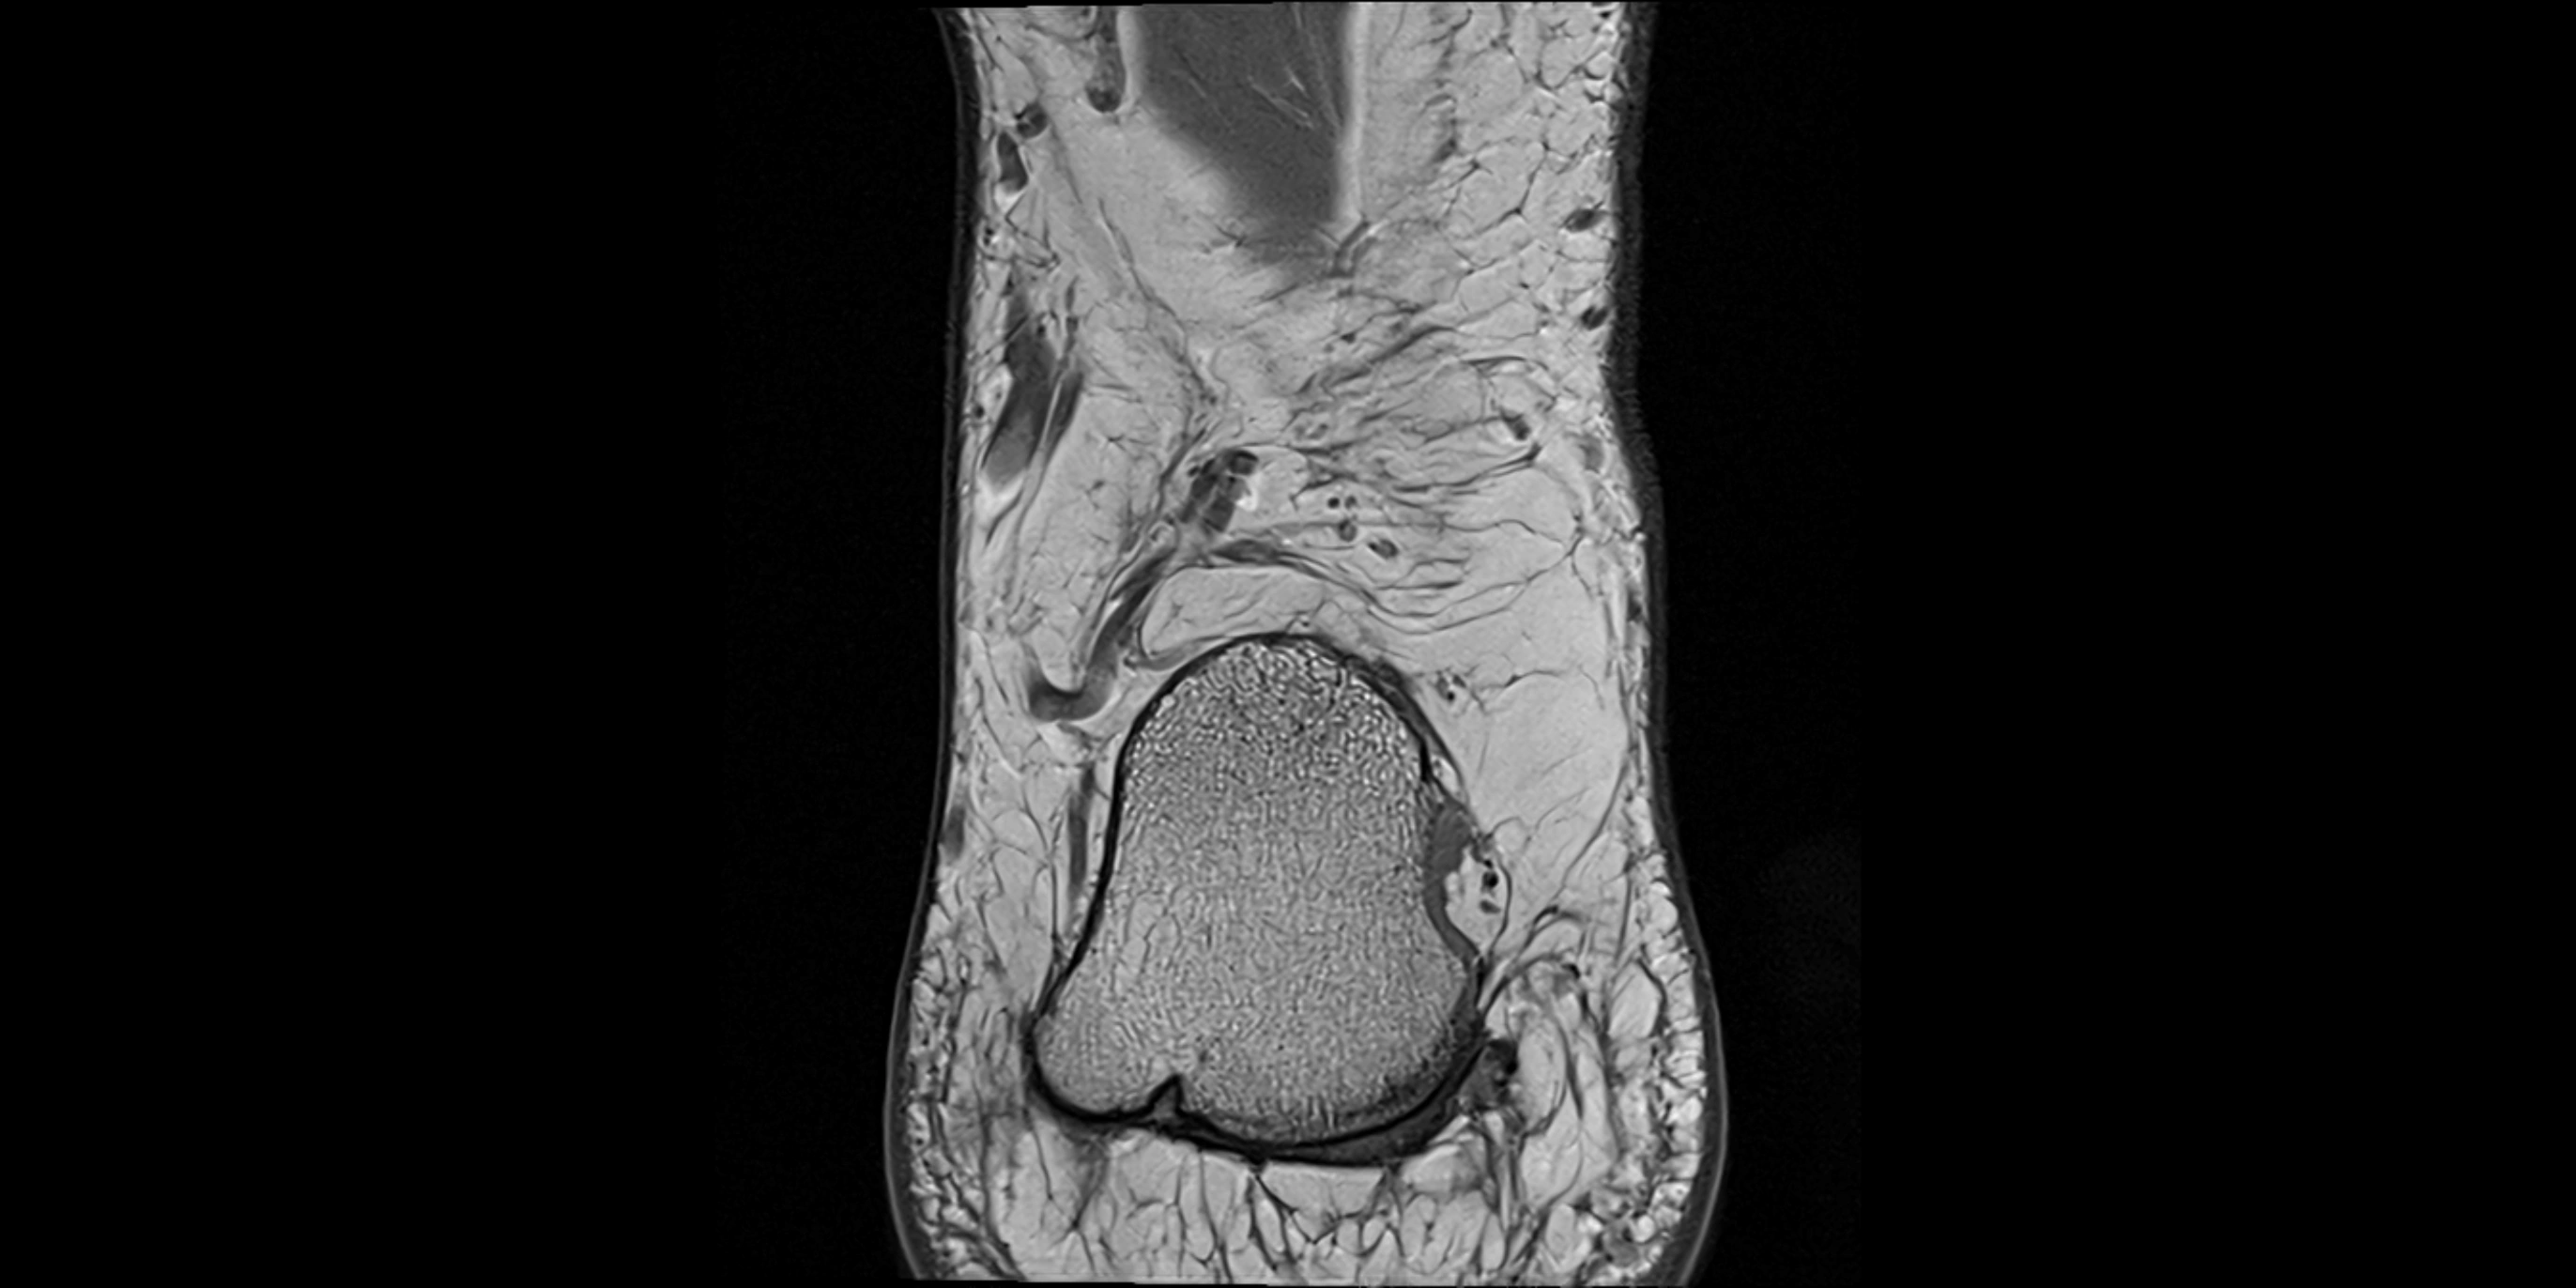

MRI image

image